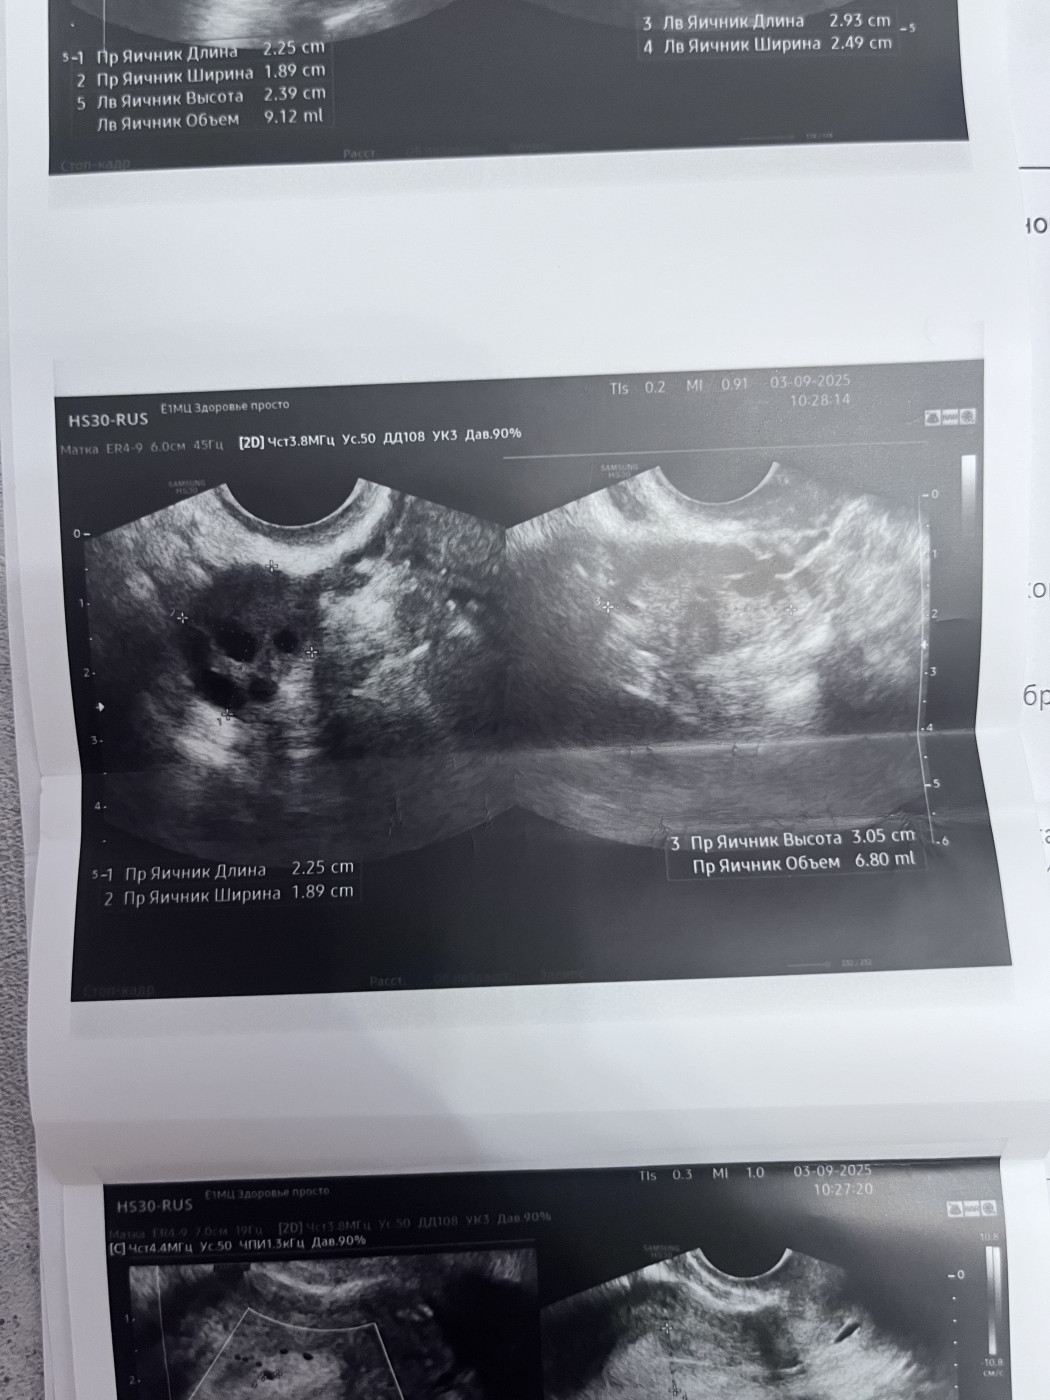

Результаты УЗИ

Миома матки

Киста, странные результаты повторного УЗИ